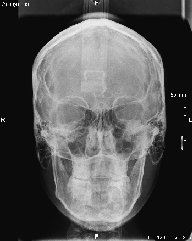

• Telerradiografía frontal y lateral digital

• Ricketts frontal

Algunos ejemplos de imágenes digitales

Pulse en las imágenes para ver la ampliación

anciano-fte